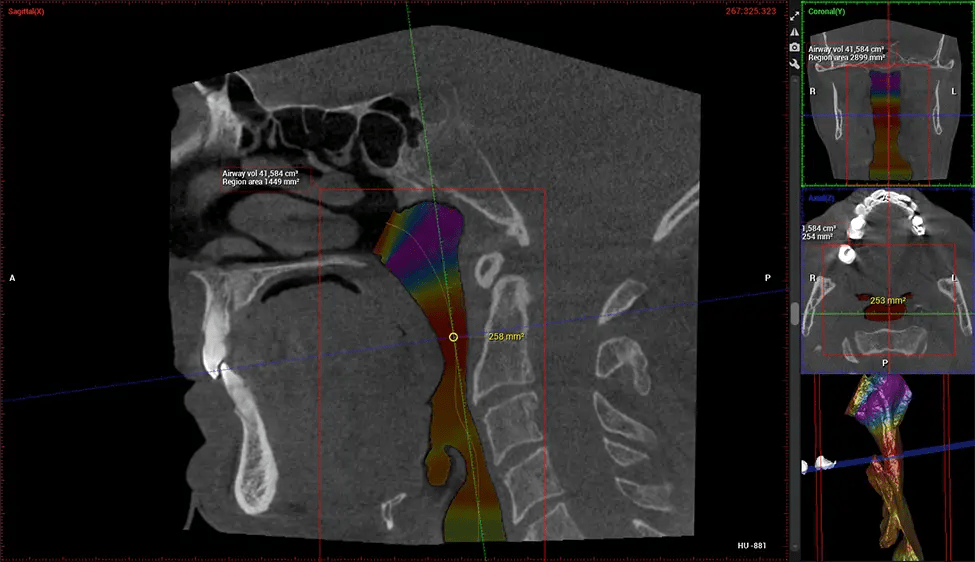

This 3D scan, called cone beam computed tomography, gives your dentist a more complete image of your oral anatomy and disease processes than a traditional X-ray. Unlike conventional X-rays, which capture a 2D image of your mouth from various angles, a 3D scan takes multiple digital X-rays for one image. It provides a complete view of your jaw, teeth, nerves, and soft tissues. This enhanced view allows dentists to detect minor issues not visible in traditional 2D scans, such as impacted wisdom teeth or bone fractures in the sinus cavity.

There are many benefits to using CBCT technology, especially compared to the traditional 2D X-ray format. One of the most significant advantages of CBCT scans is that they provide much more information than traditional X-rays. A scan lets your dentist see images from all angles of your jaw and mouth, including your sinuses, nasal cavity, cheekbones, and other surrounding areas. This added information helps your dentist craft a comprehensive treatment plan that addresses all aspects of your oral health.

Another significant benefit is that 3D imaging provides more precise images of your bone structure. These images are more detailed, providing you with a more accurate diagnosis. An accurate diagnosis means better treatment for you.

After the scanning process, the captured X-ray images are processed by the CBCT software, which applies algorithms to reconstruct a detailed 3D image of the scanned area. The software compiles these individual X-ray images and creates a digital 3D representation of the patient’s anatomy. The reconstructed 3D CBCT image can be viewed and analyzed by the dentist or radiologist. This image can be manipulated, rotated, and zoomed in or out to examine specific structures and evaluate the patient’s condition.